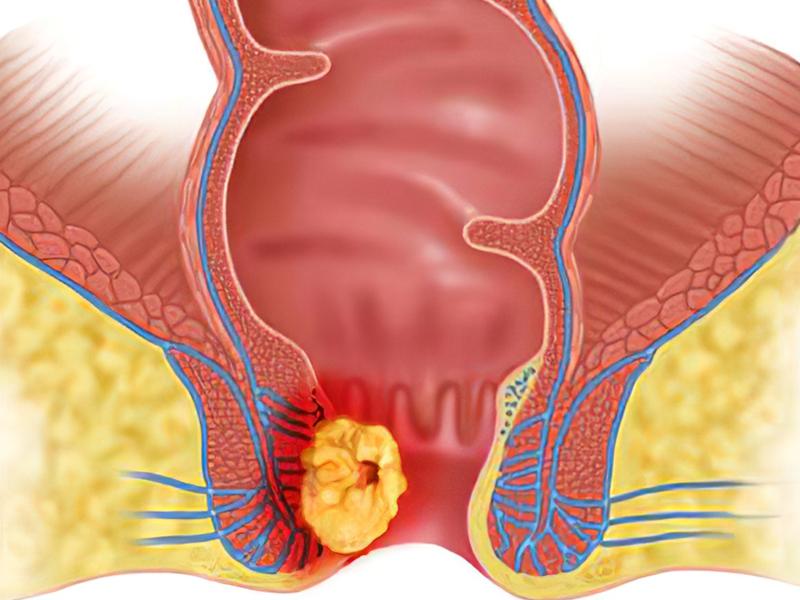

瀏覽:34125 肺部有癌,雙腳先知?同時出現 4 現象,癌症或已到了中晚期 | 瀏覽:11843 體內有癌,肛門先知 | 瀏覽:5444 別不當回事!這 6 種小病,很多人最後拖成了癌 |